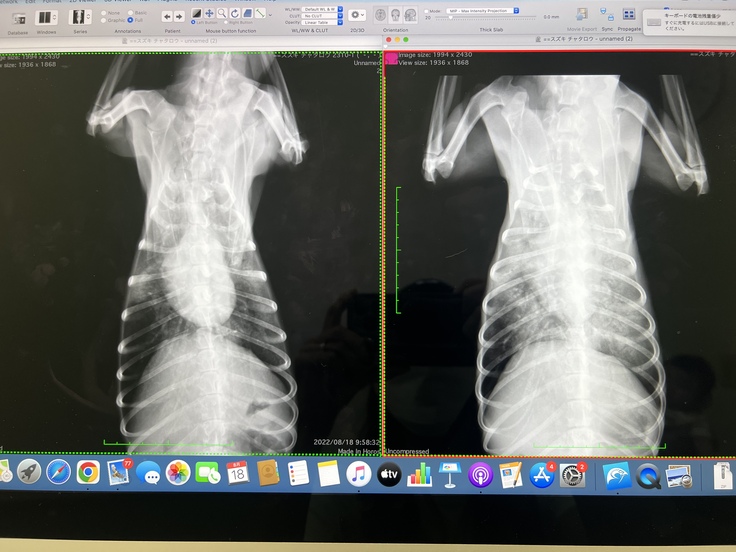

8/18 2回目の抗がん剤治療の日です。

血液検査とレントゲンを撮っていただき前回の抗がん剤がどれほど効いているのか調べて頂くと

癌細胞でかなり白く影になっていた肺は抗がん剤の効果で正常な黒色へと戻りつつあり

血液検査の結果も前回と比べて良い数値になってきていると言っていただけました。

↑ 左:抗がん剤治療後 右:治療前

(資料の掲載許可は得ています)